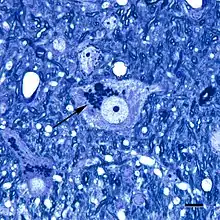

Lipofuscin is the name given to fine yellow-brown pigment granules composed of lipid-containing residues of lysosomal digestion.[1][2] It is considered to be one of the aging or "wear-and-tear" pigments, found in the liver, kidney, heart muscle, retina, adrenals, nerve cells, and ganglion cells.[3]

Lipofuscin appears to be the product of the oxidation of unsaturated fatty acids and may be symptomatic of membrane damage, or damage to mitochondria and lysosomes. Aside from a large lipid content, lipofuscin is known to contain sugars and metals, including mercury, aluminium, iron, copper and zinc.[4] Lipofuscin is also accepted as consisting of oxidized proteins (30–70%) as well as lipids (20–50%).[5] It is a type of lipochrome[6] and is specifically arranged around the nucleus.